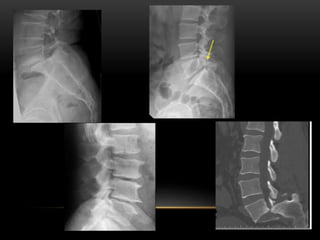

DIAGNOSIS

• X Rays

• Ap View … Napolean Hat Sign

• Lateral View

• Oblique Views… Scottish Dog With Collar Sign

• Flexion And Extension Lateral Views …

For Segmental Instability

FLEXION AND EXTENSION VIEWS